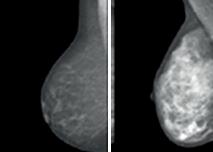

Till vänster: ett bröst med låg mammografisk täthet.

Till höger: ett bröst med mycket hög täthet.

Risken för bröstcancer är 4-6 gånger större för kvinnor med mycket täta bröst som på bilden längst till höger.

Risken för bröstcancer är mycket större för kvinnor med mycket täta bröst

vilket cirka 10 procent av Sveriges kvinnor har. Därför behövs nya rutiner, där bröströntgen bör skräddarsys utifrån varje kvinnas sammantagna risk.

MEN ÄVEN OM alla kvinnor gick på sin mammografi skulle vi ändå ha fortsatta utmaningar att upptäcka alla bröstcancrar tidigt. Risken för bröstcancer påverkas av en mängd faktorer och bröst med tät körtelvävnad är mer svårundersökta än andra. Brösttätheten utgörs av bröstkörtelvävnad och bindväv. Bindväven och körtelvävnaden är vit på en mammografibild. Det svarta på en mammografibild är fettvävnad. Täta bröst gör det både svårare att hitta eventuella tumörer på mam-

mografibilderna och försenar därmed diagnosen. Samtidigt växer tumörer ofta i körtlarna.